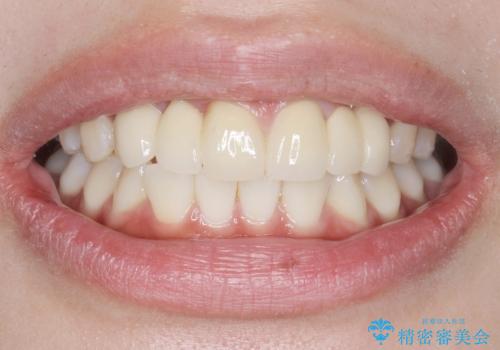

自然な仕上がりにご満足頂けました。

治療終了後、奥歯に残っていた矯正の接着剤を除去し、ホワイトニングも行いました。

クラウンの種類:オールセラミッククラウン スタンダード